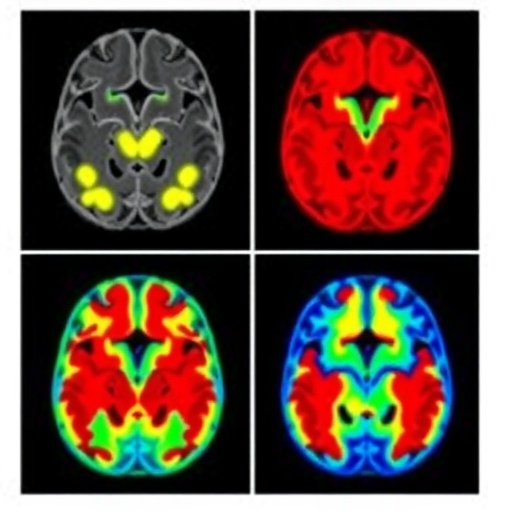

Utilizing structural and functional magnetic resonance imaging (MRI) data from a substantial cohort of adolescents, the researchers applied a novel semi-supervised learning framework designed to integrate labeled and unlabeled data. This approach allowed for the identification of subtle, yet clinically relevant, neural variations that may be overlooked by purely supervised or unsupervised methods. The resultant clustering revealed several distinct neuroimaging subtypes exhibiting unique patterns of brain morphology and connectivity.

One of the main findings of the study is the discovery of at least three neuroimaging subtypes within the adolescent ADHD population. Each subtype demonstrated differential alterations in key brain regions implicated in attention regulation, executive function, and impulse control. For example, one subtype exhibited marked reductions in prefrontal cortical thickness combined with hyperconnectivity in subcortical circuits. In contrast, another subtype showed widespread cortical thinning but hypoactivity in networks responsible for cognitive control. These neuroanatomical distinctions corresponded with variable clinical symptom severity and cognitive performance profiles.

Technically, the study leveraged high-resolution multimodal MRI sequences and advanced preprocessing pipelines, ensuring data quality and reproducibility. The machine learning models implemented neural network architectures capable of capturing non-linear relationships within high-dimensional imaging data. Cross-validation techniques and independent replication cohorts were employed to validate findings, underscoring the robustness of the neuroimaging subtypes identified.